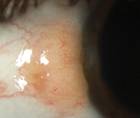

Unraveling the Role of Accessory Lacrimal Glands

Srinivas Sai Kondapalli, MD; Nandini Venkateswaran, MDSrinivas Sai Kondapalli, MD; Nandini Venkateswaran, MD - Ocular Surface